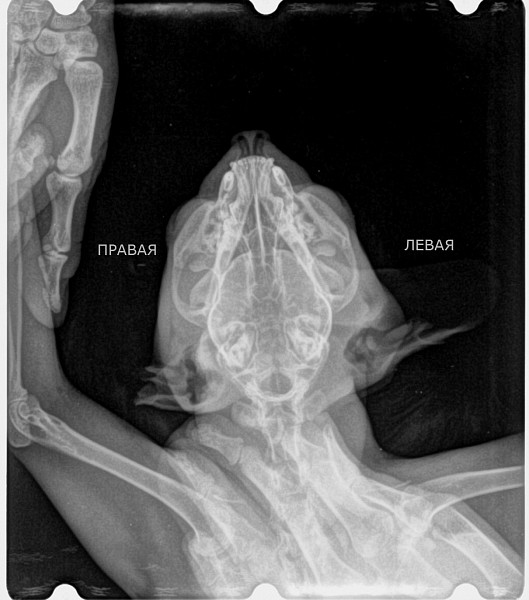

Рентгеновские снимки головы кошки в боковой проекции